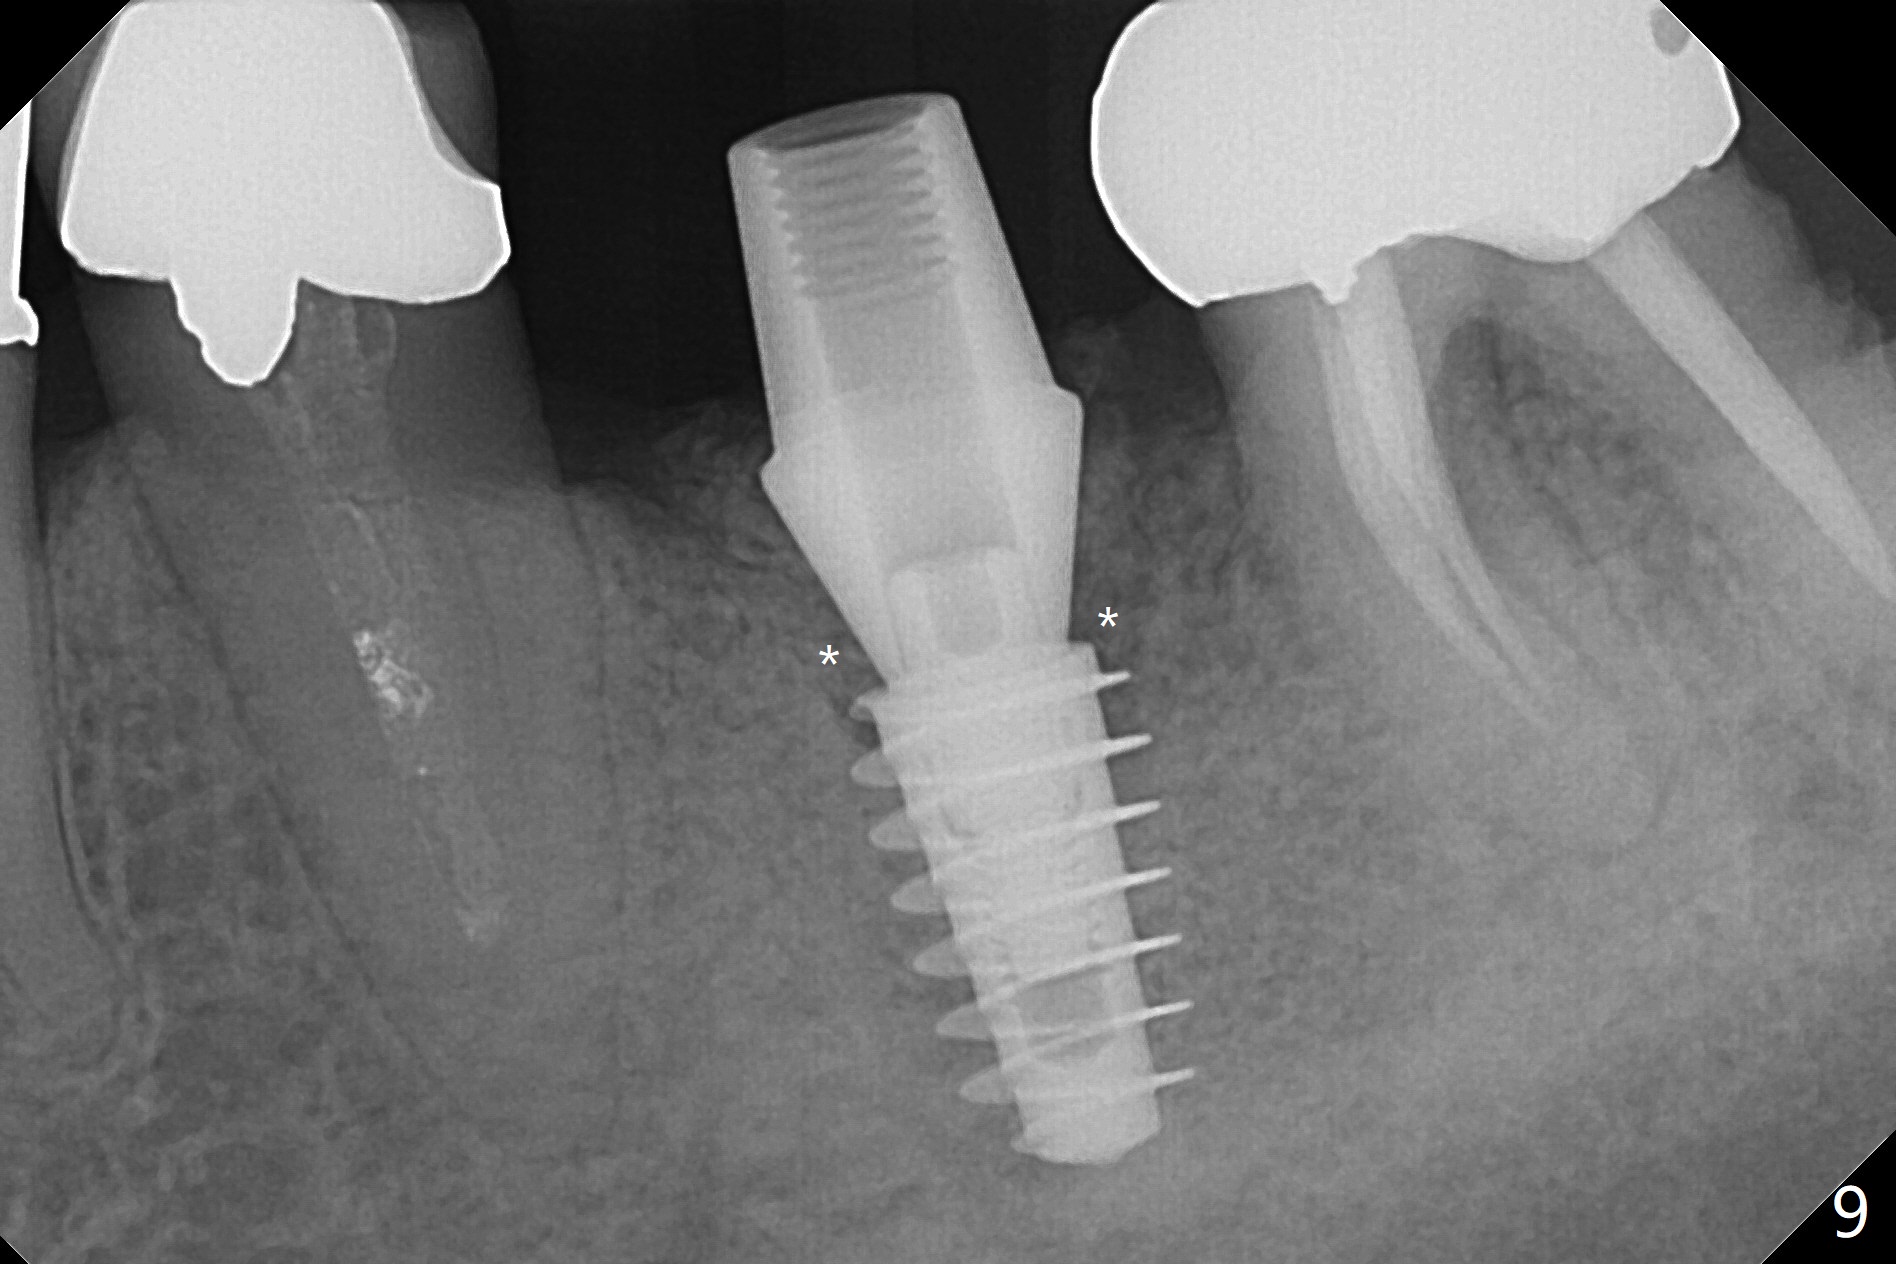

When the patient returns 4 months post implant removal and bone graft, the ridge at #19 is concave with a small hole which communicates with the underlying bone (Fig.1 <). The low density bone in the middle of the socket is ignored (Fig.2 *, 3 S (soft)). With under drilling, primary stability of tissue-level taps is lower. A bone-level dummy implant is placed with low torque (Fig.4). After removal of granulation tissue distal to the osteotomy, a larger implant is inserted with ~15 Ncm; mixture of autogenous bone and allograft is packed (Fig.5 *). The latter is covered by 12x12 mm BioXclude and sutured with 4/0 Chromic Gut tension free. 植牙后6.5月牙槽嵴饱满,角化龈宽(图六(刚开始浸润麻醉))。术后6.5月切开证实植体上面没有骨质覆盖(如图七:*),第一螺纹可能暴露(>)。由于骨质吸收,大号基台置入没阻挡,或者困难(图八),第一螺纹暴露(>)需要再次植骨(图九:*)。放置大号基台(6x6(4)毫米)和植骨使萎缩牙槽嵴部分得到修复(图十,与Uncover前(图六)对比)。Uncover时即刻置入修复性基台好处是利用基台牙龈外部分强化牙周敷料固定,基台中央放置一个棉球后,敷料可以插入基台中央进一步增加固位(图十一(舌侧观):*)。